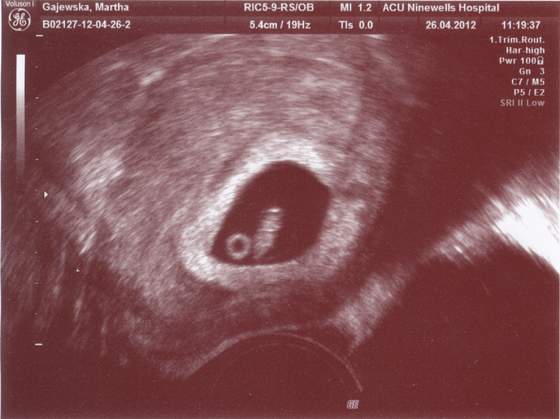

Bliźniak drugi 9,6mm

Zobacz załącznik 459765